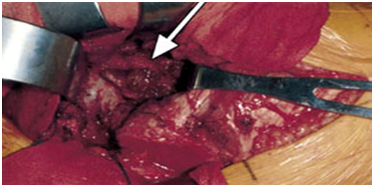

Grossly, pigmented villonodular synovitis appears as a proliferative synovial process with brownish villo-nodular fronds in the affected joints (Figure 3).2 Multiple yellow to brown nodules could be detected in localized types and in the pes anserine bursa (Figure 4). Histopathologically, the tumor is generally represented by many mononuclear histiocytic cells and irregularly interspersed multinucleated giant cells. Hemosiderin pigments could also be detected. Some foamy histiocytic cells may individually interspersed or form clusters (Figure 5).8 Osseous, cartilaginous, and soft tissue involvement was also seen .Fine needle aspiration cytology reveal a few clustered and scattered plump spindle cells containing hemosiderin-pigments and several scattered multinucleated giant cells (Figure 6).

Figure 3 Photograph showing characteristic hypertrophic synoviumv (arrow) and villo-nodular fronds in pigmented villonodular synovitis.